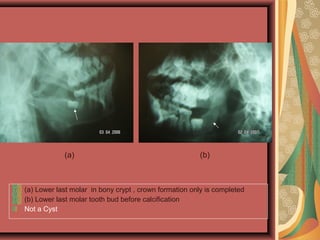

(a) Lower last molar in bony crypt , crown formation only is completed

(b) Lower last molar tooth bud before calcification

Not a Cyst